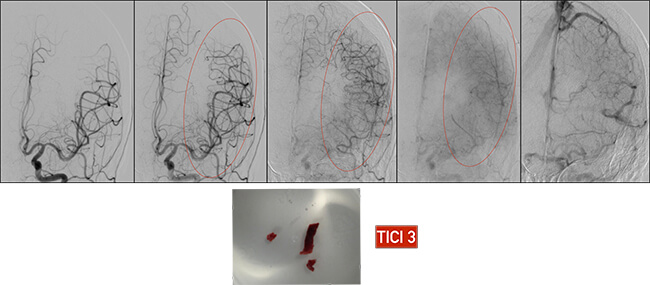

Αφού το stent-retriever βγεί έξω από τον οδηγό καθετήρα, ξεπλένουμε τον οδηγό καθετήρα και επιθεωρούμε το stent-retriever και τον θρόμβο που έχει προσκοληθεί πάνω του. Αποκαθιστούμε την ροή στον οδηγό καθετήρα ξεφουσκώνοντας το μπαλόνι. Αγγειογραφούμε από τον οδηγό καθετήρα γιά να δούμε εάν αφαιρέθηκε όλος ο θρόμβος και εάν έχει αποκατασταθεί η ροή ή εάν υπάρχει υπολλειματικός θρόμβος. Στην δεύτερη περίπτωση πρέπει να γίνει δεύτερη προσπάθεια θρομβεκτομής με το ίδιο stent-retriever. Συνολικά μπορούμε να επιχειρήσουμε μέχρι και τρείς προσπάθειες θρομβεκτομής.

Στην προκείμενη περίπτωση της ασθενούς, ο θρόμβος έχει πλήρως αφαιρεθεί και η μέση εγκεφαλική αρτηρία έχει πλήρως επανασηραγγοποιηθεί με αποκατάσταση της αιματικής ροής προς τον εγκέφαλο (κόκκινος κύκλος).

Η όλη επέμβαση από την μηριαία παρακέντηση μέχρι την ανάκτηση του θρόμβου είχε διάρκεια 25 λεπτών.